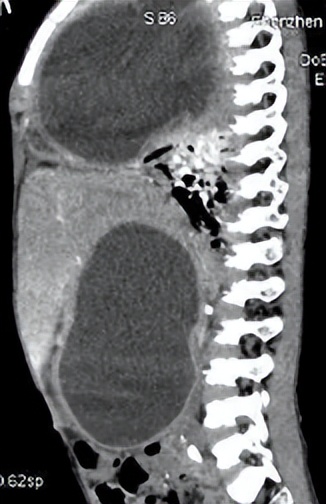

话不多说,医生给京京开了CT检查单。检查结果出来后,在场的人无不感到惊讶:

右侧胸腔和腹腔居然各有一个巨型囊肿。

由于囊肿已经严重压迫到肺部,导致男孩呼吸困难,随时都有生命危险。说得直白点,就是京京已经一只脚踏进了鬼门关。